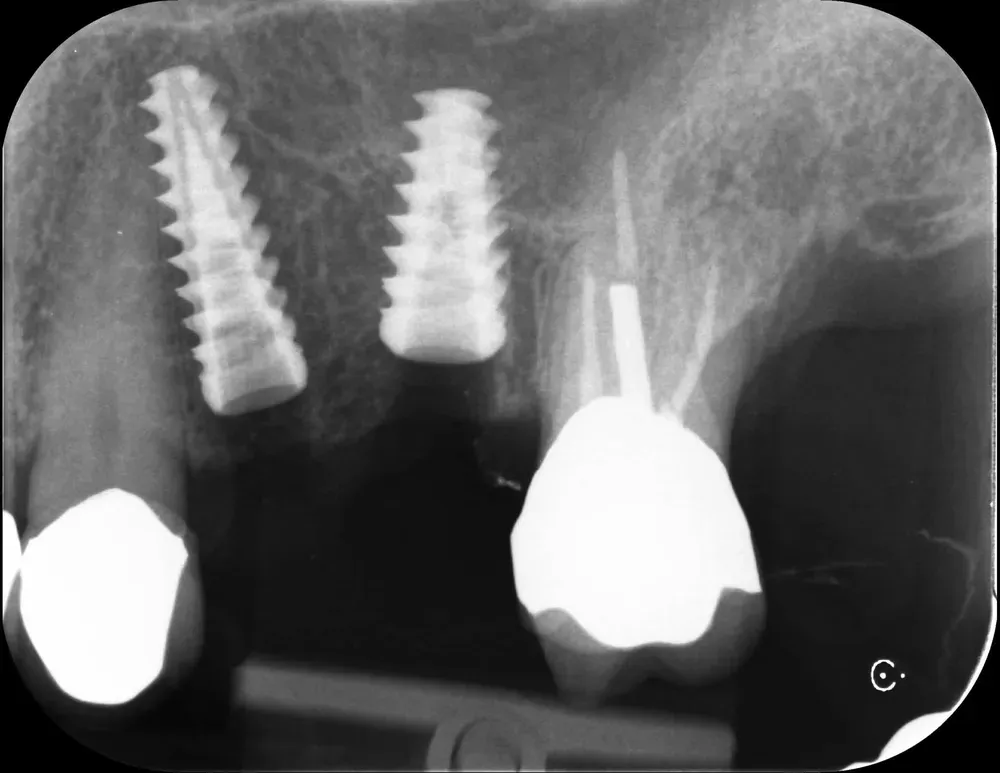

Di seguito, le radiografie periapicali mostrano gli impianti appena inseriti e gli abutment con i provvisori.

Rx Periapicale Post-op

Rx Periapicale con abutment e provvisori